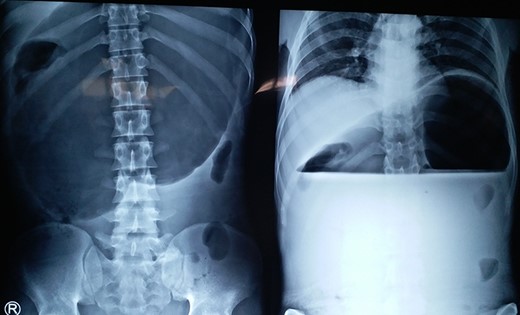

X-ray showing a markedly distended and spherical stomach suggesting gastric volvulus.

A 25-year-old-male presented to emergency department with 2 days of abdominal pain and non-bilious vomiting. His vitals were stable. The abdominal examination revealed epigastric fullness. There was no tenderness or organomegaly. The laboratory investigation showed normal hemoglobin (12.6 gm/dl), leukocytosis (18 200 cells/mm3) and normal renal function test and serum chemistry. Chest and abdominal X-ray showed elevated left hemi-diaphragm, grossly dilated and spherical stomach with large air-fluid level occupying whole of the upper abdomen (Fig. 4). The diagnosis of gastric volvulus was made and further confirmed by CT. Nasogastric decompression was attempted, but was futile. Patient was resuscitated, injectable broad-spectrum antibiotic commenced and planned emergency laparotomy. At surgery, organo-axial gastric volvulus was seen lying totally in the abdominal cavity, which was de-rotated and series of anterior abdominal wall suture gastropexy performed to prevent recurrently. The patient had an uneventful postoperative course. He was discharged on Day 7. At 28 months follow-up, the patient is asymptomatic.